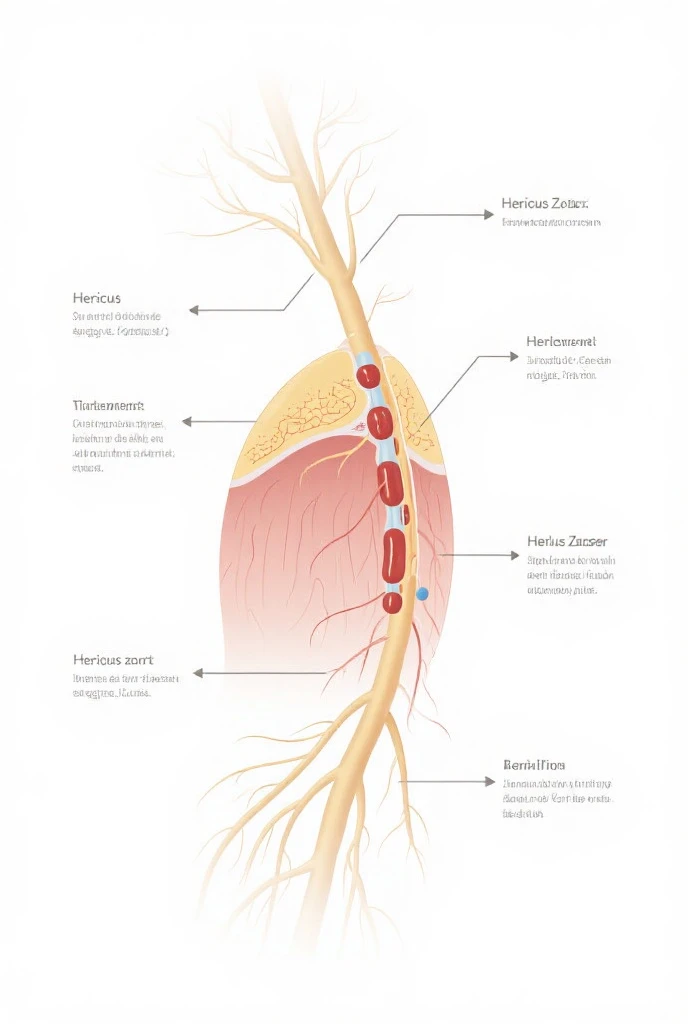

A diagram of the anatomy of the human body

Epidermis Fermis Hypodermis Keratinized squamous stratified epithelium Hair Sebaceous gland Sweat gland Pilo erector muscle Connective tissue Blood vessels Nerves Adipocytes